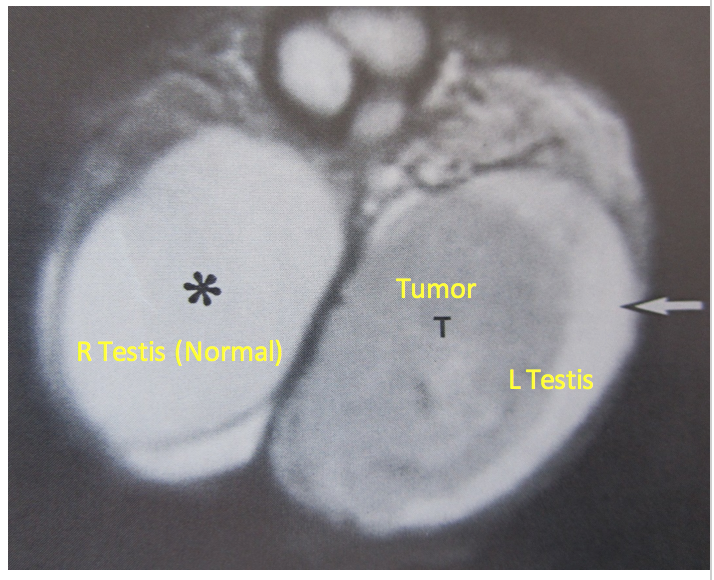

What do the letters represent?